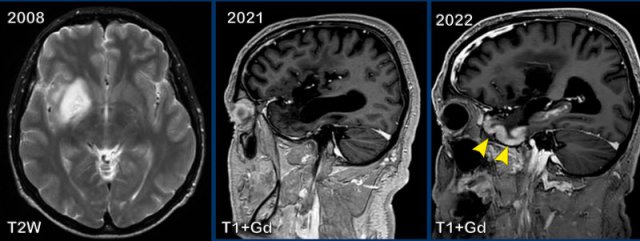

These images are of a 59-year old man, who had a partial resection of a glioma in 2008.

In 2016 there was progression of the tumor which was treated with radiotherapy followed by chemotherapy.

In 2021 there was no sign of residual tumor and in 2022 this patient presented with migraine.

Images

In 2008 a tumor is seen as a lesion with high signal on T2W

at the right basal ganglia and insular region.

In 2021 everything is stable, but in 2022 there is gyral

enhancement of the grey matter of the temporal lobe (arrowheads).

Continue with two more images of this patient...

DWI shows cortical diffusion restriction in the right temporal lobe.

The sagittal T1W+Gd-image at a different level again shows the gyral enhancement pattern.

This is called SMART (Stroke-like Migraine Attacks after Radiation Therapy).

It is an uncommon delayed complication of cerebral radiation therapy characterized by cortical swelling and gyral enhancement.

These patients usually present with migraine, but seizure and hemiparesis is also a possible presentation.

In the context of prior brain radiotherapy this should raise the suspicion of SMART syndrome.

Prompt diagnosis is essential to avoid unnecessary invasive investigations.

It is a self limiting disease.

It is a diagnosis per exclusionem and you have to rule out ischemia, PRES and seizures.